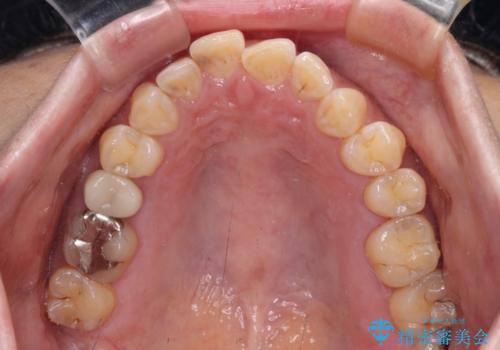

- 飛び出た上の前歯を気にして来院された患者様です。

奥歯の咬み合わせは、上顎歯列が理想的な一よりも数mm前方にある状態でした。

なるべく早めに治療を終えたいとのことで、補助装置を用いて上顎臼歯を後方に移動させ、同時にワイヤー装置にて整えることとしました。

舌の突出癖が原因で上下の歯に大きなスペースが生じていたため、舌のトレーニングをしっかり行っていただくことで、上顎歯列をスムーズに移動させることができました。